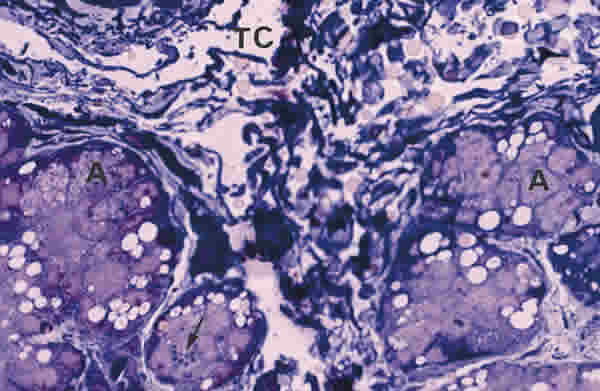

Figura 15

BIOPSIA EN UN PACIENTE CON QCS-GRADO III. LOS ACINOS (A) DE LA GLÁNDULA LAGRIMAL PRINCIPAL ESTÁN CONSTITUIDOS POR CÉLULAS MUY ALTERADAS CON ESCASO NÚMERO DE GRÁNULOS DE SECRECIÓN (FLECHA ARRIBA). eL TEJIDO CONECTIVO INTERSTICIAL (TC) ES AMPLIO Y DENSO. TINCIÓN AZULES DE RICHARDSON. MAGNIFICACIÓN ORIGINAL X100.